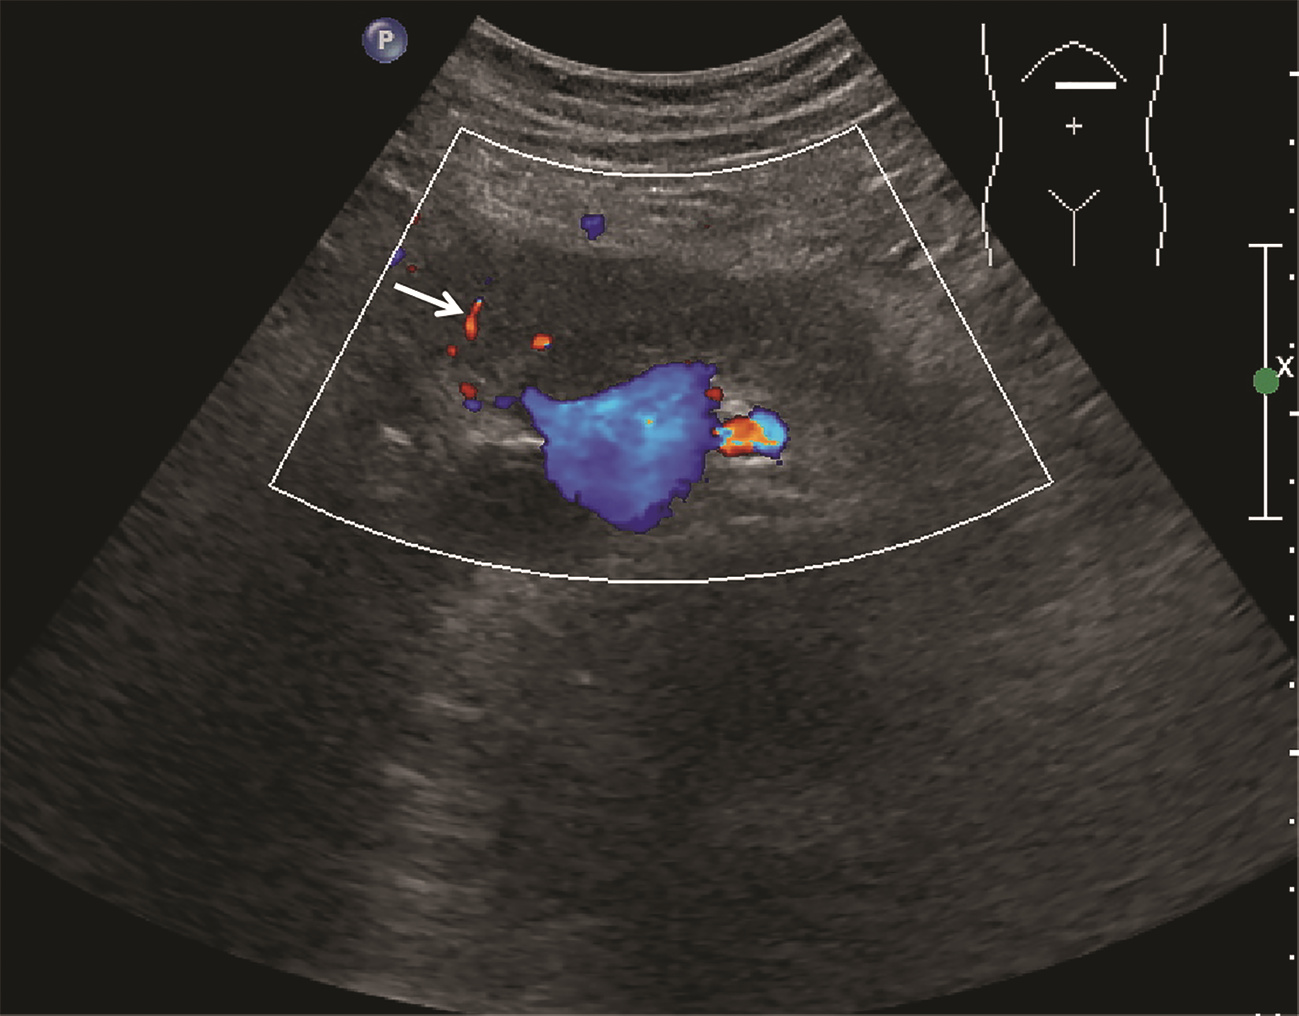

肿块型自身免疫性胰腺炎与胰腺导管腺癌的超声及超声造影表现分析

欧阳向柳, 韩云霞, 郑立春, 赵英春, 申新宇, 张文军, 王艳滨

2022, 38(6): 1351-1355. DOI: 10.3969/j.issn.1001-5256.2022.06.025

摘要(1431) HTML (553) PDF (3738KB)(51)

摘要:

目的  探讨超声及超声造影对肿块型自身免疫性胰腺炎(AIP)与胰腺导管腺癌(PDAC)的鉴别诊断价值。  方法  回顾性分析2015年1月—2020年12月唐山市工人医院确诊的11例肿块型AIP患者的临床资料及常规超声、超声造影资料,分析其特征性表现,并与23例PDAC患者的资料进行对比,计数资料两组间比较采用χ2检验。  结果  11例肿块型AIP超声造影的诊断准确性为63.64%,均为单发病灶,且均低回声,在边界清晰、形态规则、胰管扩张或截断、血流信号方面所占比例分别为54.55%、63.64%、18.18%、36.36%,而PDCA组分别为30.43%、34.78%、78.26%、21.74%,两组间是否伴胰管扩张或截断方面存在统计学差异(χ2=11.089,P<0.05),其余指标均无明显统计学差异(P值均>0.05)。超声造影中7例(63.64%)肿块型AIP动脉期呈高增强,4例(36.36%)呈等增强,静脉期5例(45.45%)呈高增强、6例(54.55%)呈等增强;23例PDAC中22例(95.65%)病灶在动脉期及静脉期均呈低增强,两者动、静脉期强化方式差异均有统计学意义(χ2值分别为30.345、30.084,P值均<0.05)。  结论  超声造影检查增强模式及是否伴胰管扩张或截断方面在肿块型AIP与PDCA的鉴别诊断中具有较高的价值。